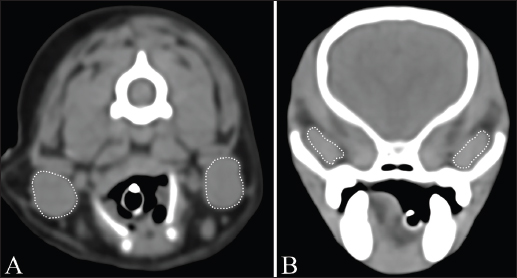

The maximum cross-sectional area (MCSA) of the bilateral mandibular and zygomatic glands was measured on non-contrast transverse CT images (Fig. 1). The region of interest (ROI) for MCSA was manually drawn including the largest area of the salivary glands. The attenuation was measured by drawing a circular ROI in each salivary gland on non-and postcontrast transverse images in all dogs (Fig. 2). The ROI was drawn as large as the anatomic configuration within each salivary gland, with the exception of obvious vascular areas. This ROI was created thrice in each salivary gland, and the attenuation value was defined as the mean of the three values. All measurements were performed by one author with 2 years of experience in veterinary diagnostic imaging, with consultation with another author with 15 years of experience in veterinary diagnostic imaging.

Fig. 2. Measurement of attenuation value of salivary gland on non-contrast (A) and postcontrast (B) CT images. The ROI of the mandibular gland (dashed circle) is drawn as large as possible.